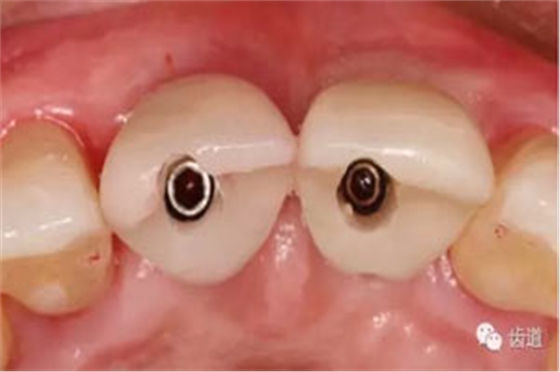

臨時(shí)冠塑形

合面觀

袖口形態(tài)

基臺(tái)就位

牙冠就位